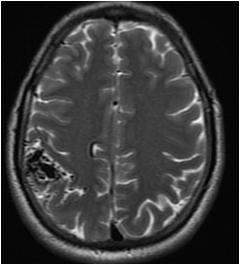

Fig 1 — CT Imaging from a patient of Basal Ganglia hemorrhage in the present study